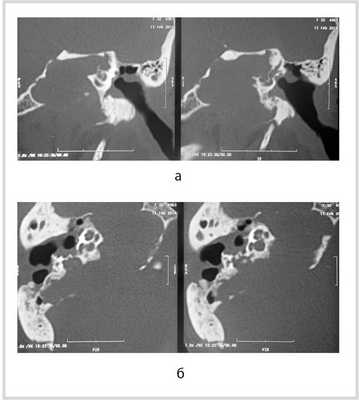

Рис. 1. КТ височных костей пациентки М. а — коронарная проекция: деструктивная полость в пирамиде височной кости, заполненная субстратом неоднородной плотности, капсула лабиринта значительно разрушена на уровне базального и апикального завитков улитки, латерального и верхнего полукружных каналов; б — аксиальная проекция: деструктивная полость с разрушением задней грани пирамиды, передневерхней и нижней поверхности.